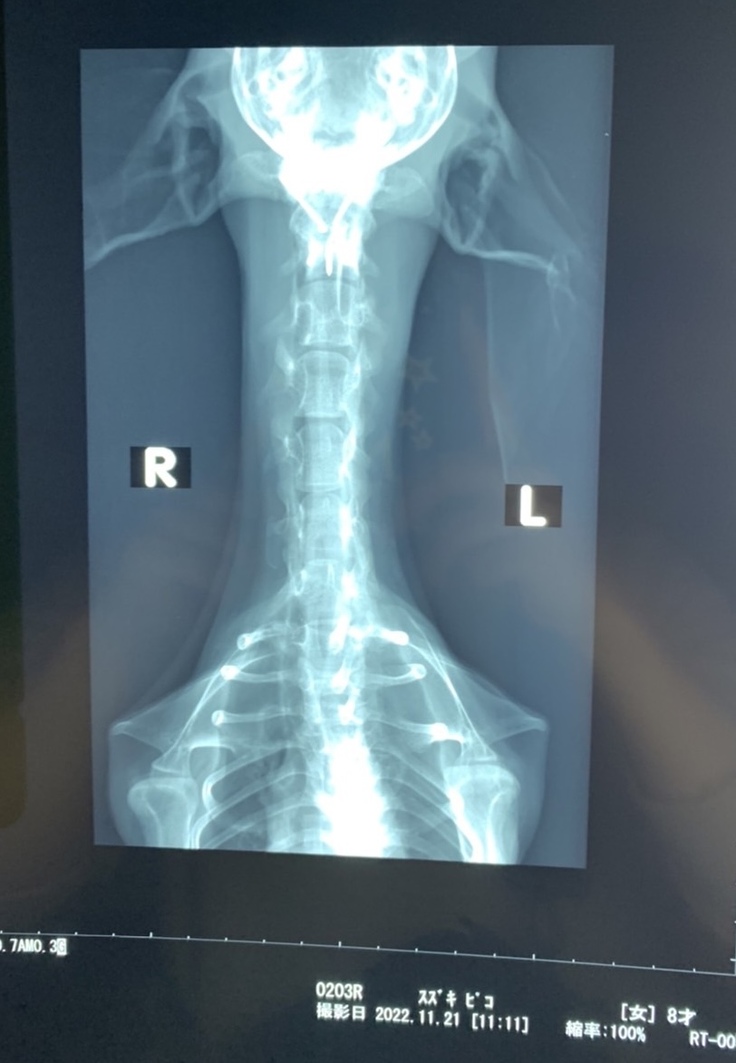

⬛︎レントゲン写真

あんなにもズレていたのが改善されています。

手術の合併症もなくとても順調です😊

█術後のレントゲン写真

術後の状態も安定しており安心しました